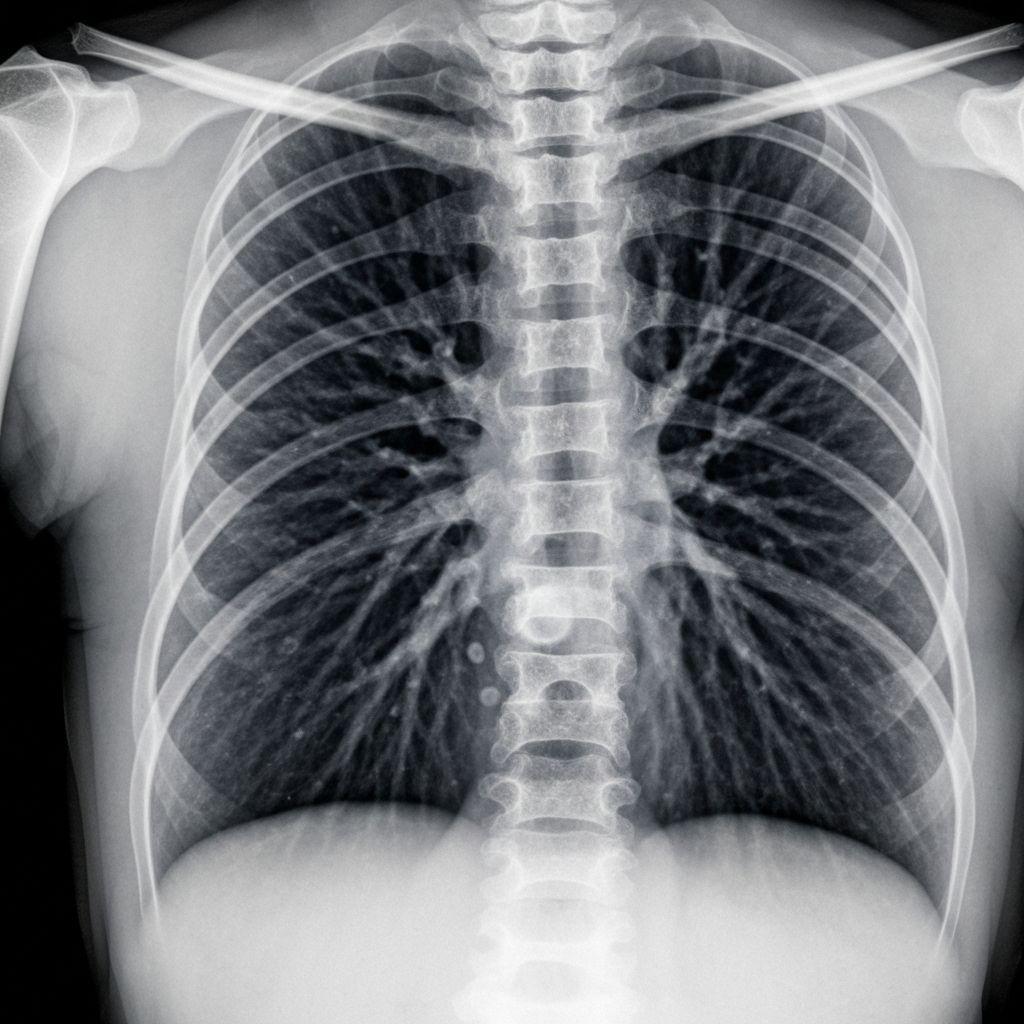

Early detection of silica dust-related lung damage through comprehensive diagnostic testing and expert medical evaluation

Chest X-ray, CT scan, pulmonary function tests, and blood work performed